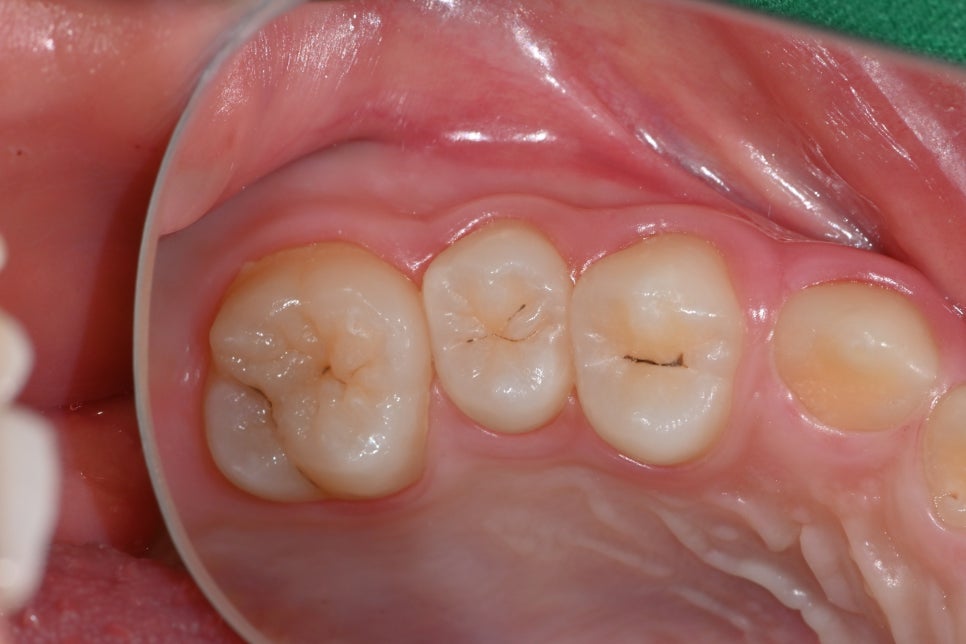

🦷 Before Treatment Photo (03.14)

This is the initial appearance of the molar with the cavity.